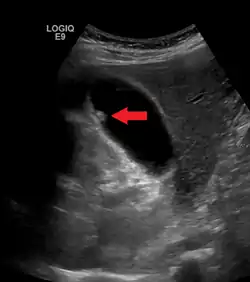

ويصف الورام العضلي الغدي الحالة المريضة للمرارة عندما يكون جدار المرارة سميكًا بشكل مفرط؛ بسبب تكاثر وانتشار الطبقة الخلوية تحت السطحية، ويتميز بوجود طيات عميقة في الطبقة العضلية. وقد يكشف التصوير بالموجات فوق الصوتية جدار المرارة السميك مع رتوج داخل العضلات، تسمى الجيوب جيوب روكيتانسكي - آشوف (بالإنجليزية: Rokitansky-Aschoff sinuses).[3]

يتم التشخيص بواسطة التصوير بالموجات فوق الصوتية، والتصوير المقطعي المحوسب.